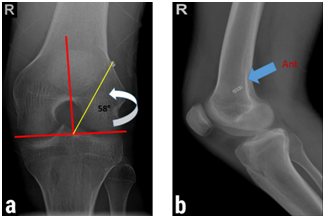

Figure 1: Correlation between the clock-face reference and the tunnel position in plain radiographs. (a) One o’clock position (high-position tunnel) in tunnel-view x-ray of the left knee. (b) The more anterior placement of the high-position femoral tunnel in comparison with low-position tunnel. (Note the endobutton insertion site.)